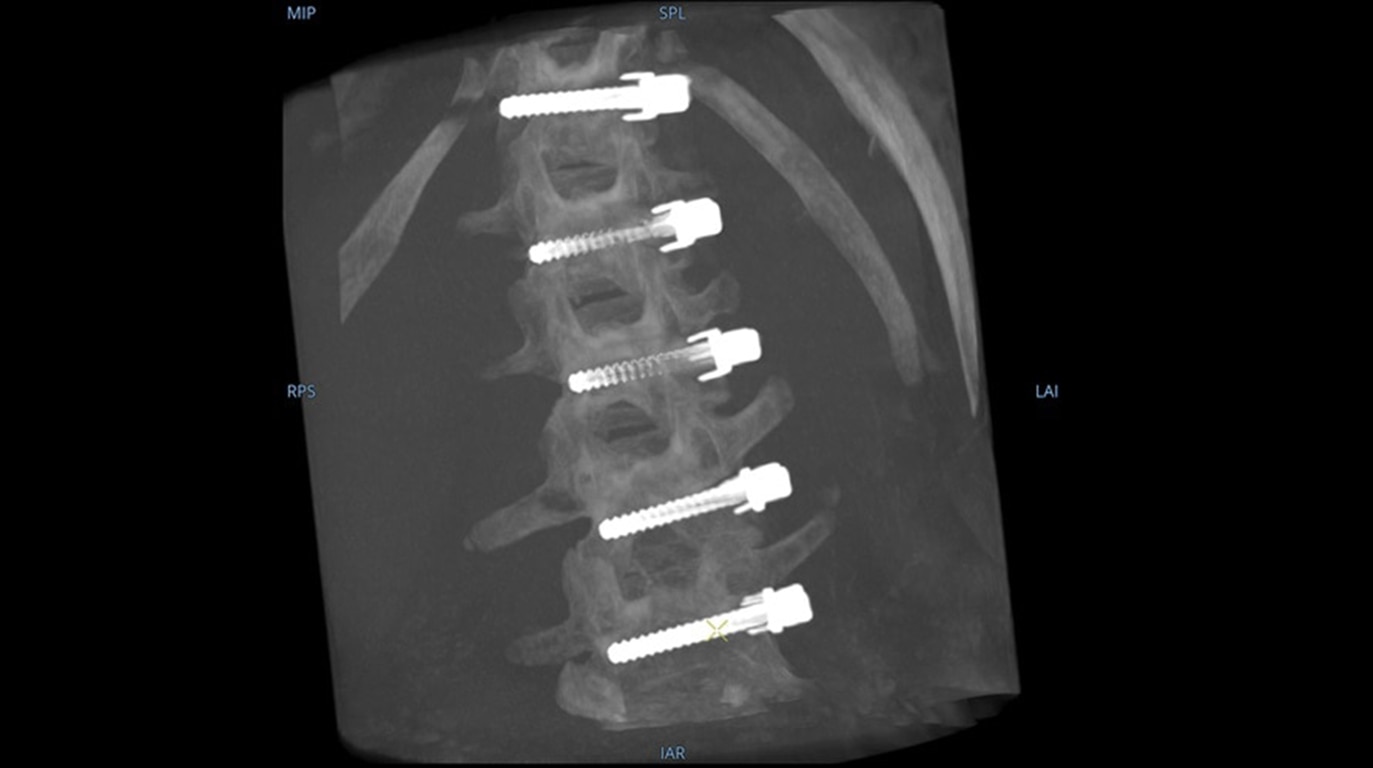

Mehr sehen, schneller entscheiden: Der OEC 3D ermöglicht die gleichzeitige Darstellung mehrerer Ebenen bei verschiedensten Anwendungen. Ob Spondylodesen, komplexe Trauma- Chirurgie oder Bronchoskopien. Mit einem Volumen von 19 × 19 × 19 cm liefert er bis zu 67 % mehr Bildinformationen als vergleichbare Systeme – für mehr Sicherheit und Effizienz im OP.

Analysieren Sie Ihre Scans mit dem GE Volume Viewer – genauso intuitiv wie am CT. Profitieren Sie von der vollständigen Darstellung axialer, koronarer und sagittaler Ebenen sowie von MIP-Ansichten und 3D-Visualisierungen im VR-Modus. Scrollen Sie durch bis zu 512 Schichten mit nahtloser Anpassung der Schichtdicke – für eine präzise Befundung direkt im OP.